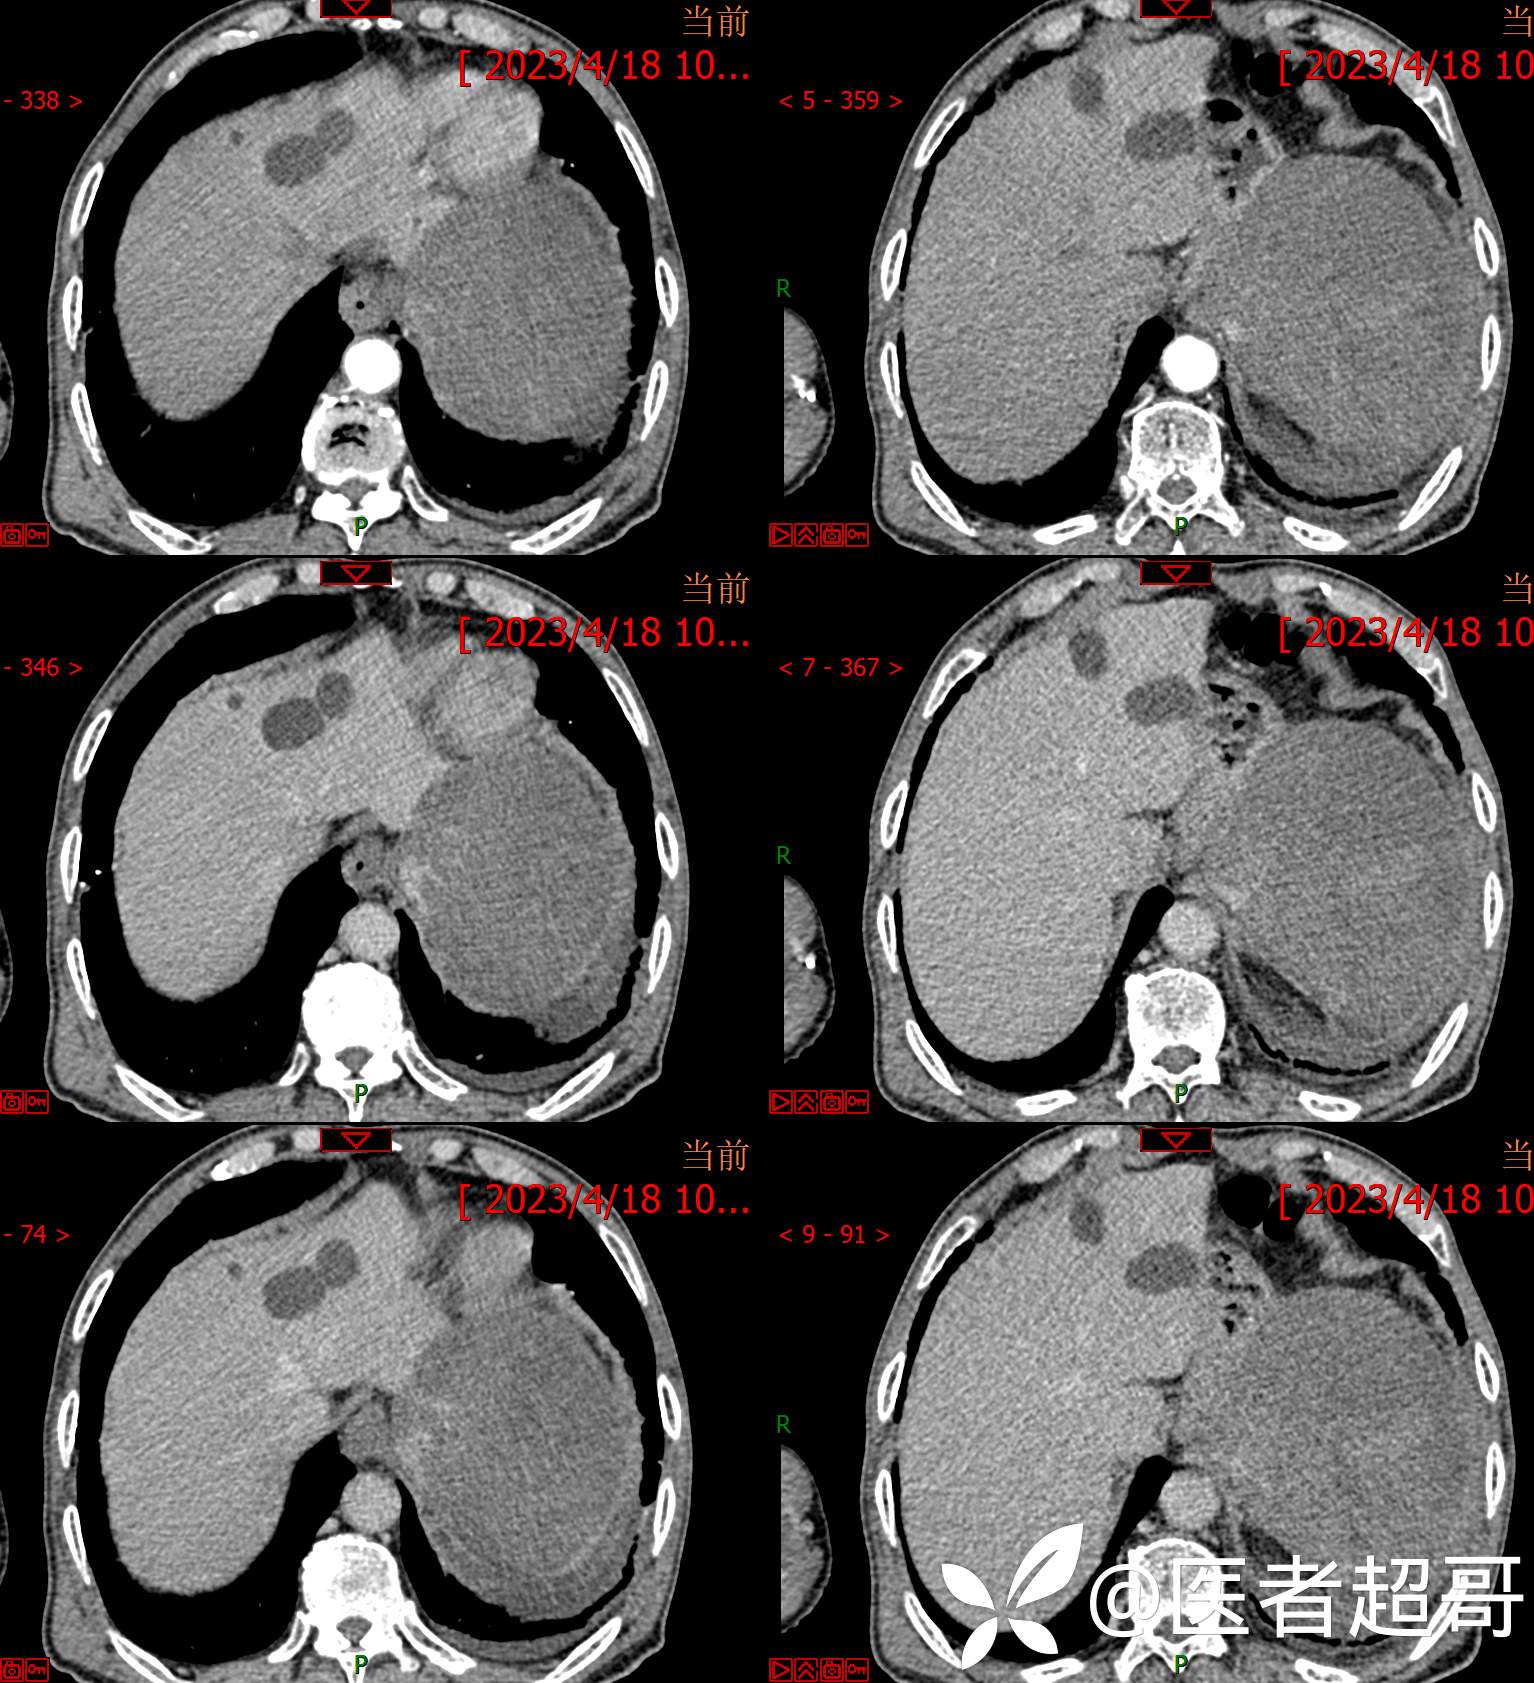

简要病史:左侧胸部疼痛不适5天就诊,临床初步诊断“肋软骨炎”。

img